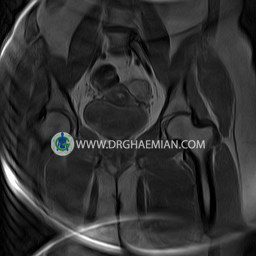

پزشکان اغلب از تصویربرداری ام آر آی برای تشخیص و درمان عارضه های پزشکی که فقط با استفاده از اشعه ایکس یا میدان مغناطیسی و امواج رادیویی قابل مشاهده است، استفاده می کنند. دستگاه ام آر آی تصاویر دقیق از ساختار های داخلی بدن ایجاد می کند. در این کیس کیست بارتولین لگن و تجمع دورمقعدی و کیست ساده ایی در تخمک چپی دیده می شود.

HIP JOINT MRI

( without contrast )

Technique : coronal STIR , coronal T2 , Axial T1 , axial T2 .

REPORT:

The femoral heads and acetabula are normal shape , signal intensity and the femoral heads are well covered by the acetabular margins .

The joint spaces are of normal width without fluid collection .

the articuler surfaces are smooth and congruent and show normal cortical thickness .

there are no marginal osteophytes or subchondral signal changes .

The bone marrow shows normal signal intensity , especially in the femoral head and neck .

Each femoral shaft has normal margins and contains a normal bone marrow signal .

– Simple cyst (28×32mm) in left ovary

– Cyst like lesion (20×25mm) in right vaginal wall suggestive for bartholin cyst and perianal collection

are seen.

COMMENT: Clinical correlation is recommended.